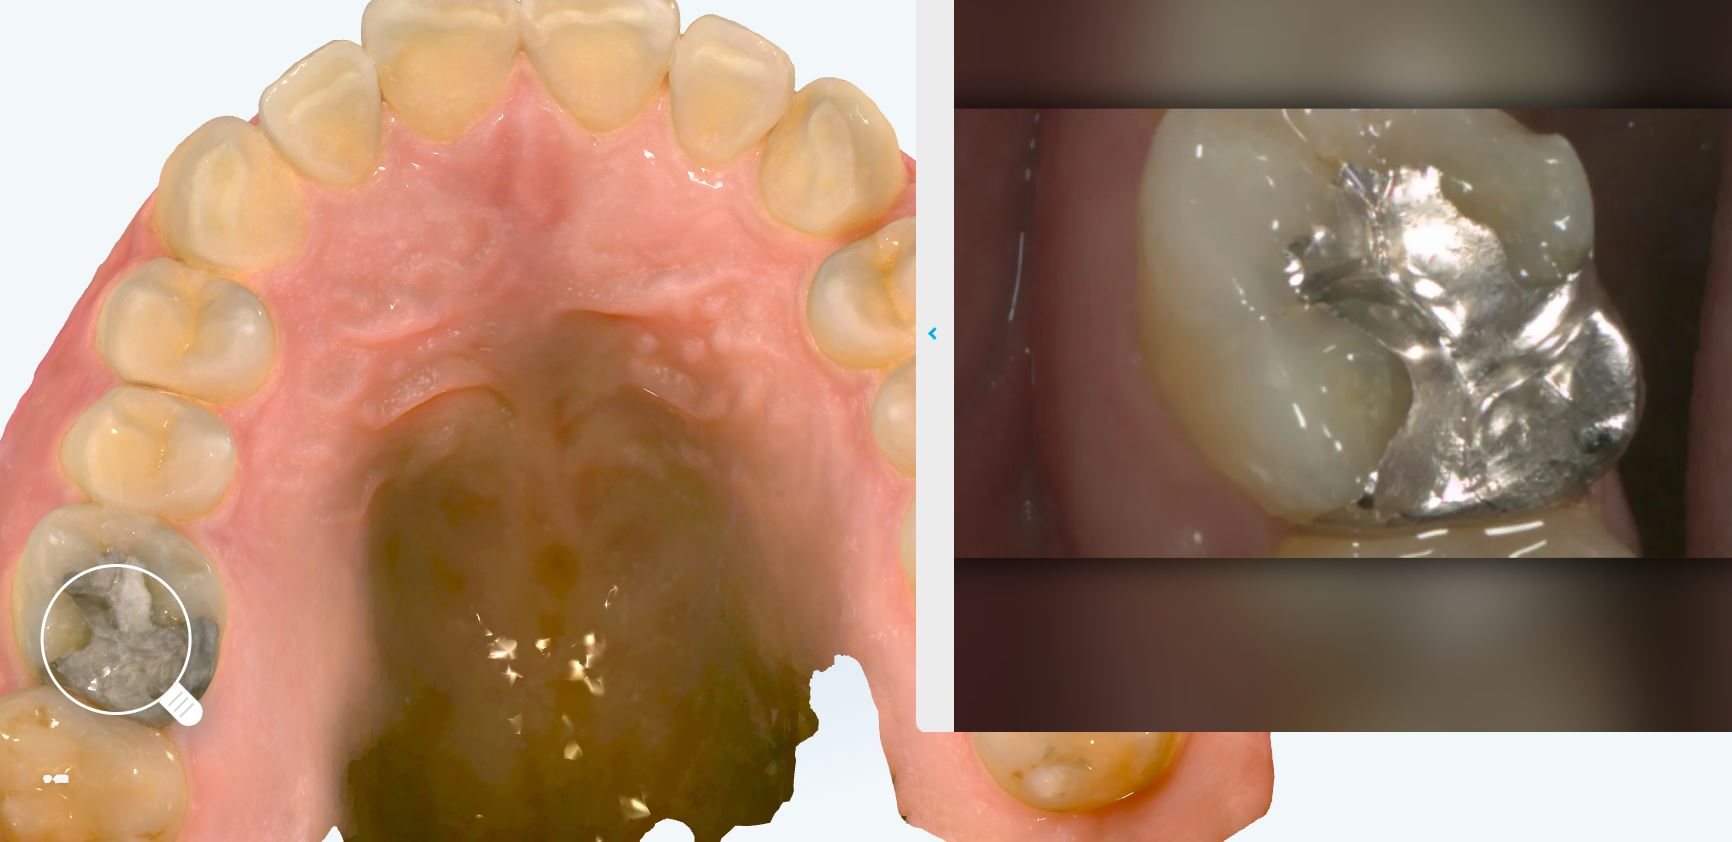

iTero Lumina(拡大画像)

拡大スキャンデータは非常に精細で、なおかつスキャナーに搭載されているカメラによって、実際の写真を映し出すことも可能です。